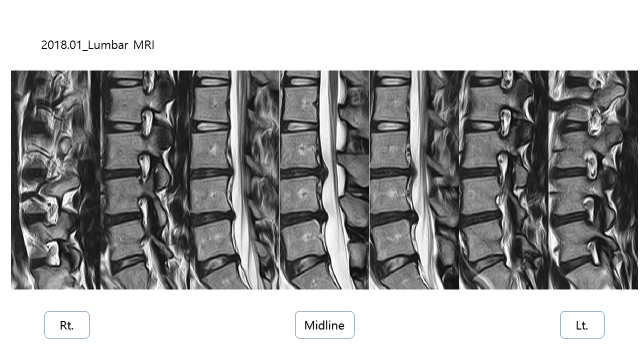

2018년도 MRI 상에서 디스크 탈출 소견이 있었음

L3/4 : DDD, Disc herniation

L4/5 : DDD, Disc protrusion

L5/S1 : bulging disc

이전에 촬영한 MRI와 비교를 하였을 때, 디스크 돌출/탈출 된 부분이 줄어든 것을 확인 할 수 있음.